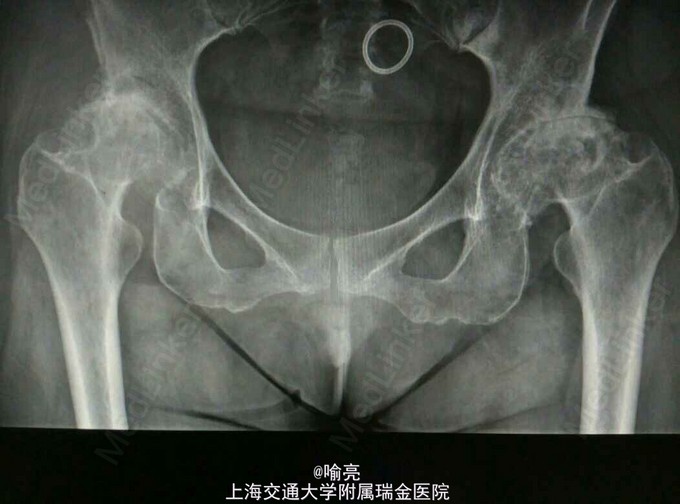

右侧腹股沟区疼痛10年。疼痛与活动相关,起病初休息后或服用止痛药物后疼痛可获得缓解。近期疼痛逐渐加重,白天活动后疼痛至夜间亦不能缓解。须长期靠止痛药物维持日常生活。

托马斯征阳性。双下肢血运感觉正常。肌力正常。 辅查:骨盆正位片提示双侧髋关节发育不良

诊断:DDH继发髋关节退变 治疗:右侧THA